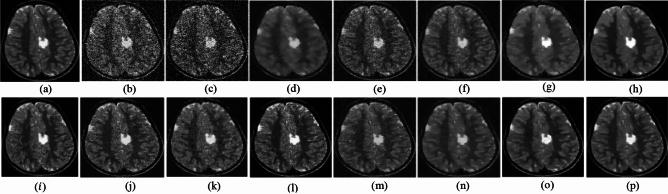

Medical imaging systems such as computed tomography (CT) and magnetic resonance imaging (MRI) are vital tools in clinical diagnosis and treatment planning. However, these modalities are inherently susceptible to Gaussian noise introduced during image acquisition, leading to degraded image quality and impaired visualization of critical anatomical structures. Effective denoising is therefore essential to enhance diagnostic accuracy while preserving fine details such as tissue textures and structural boundaries. This study proposes a robust and efficient denoising framework specifically designed for CT and MRI images corrupted by Gaussian noise. The method integrates a cluster-wise principal component analysis (PCA) thresholding approach guided by the Marchenko-Pastur (MP) law from random matrix theory and a non-local means algorithm. Noise level estimation is achieved globally by analysing the statistical distribution of eigenvalues from noisy image patch matrices and leveraging the MP law to accurately determine the Gaussian noise variance. An adaptive clustering technique is employed to group similar patches based on underlying features such as textures and edges and enables localized denoising operations tailored to heterogeneous image regions. Within each cluster denoising is performed in two stages where initially hard thresholding based on the MP law is applied to the singular values in the SVD domain to obtain a low-rank approximation that preserves essential image content while removing noise-dominated components. Residual noise in the low-rank matrix is then further suppressed through a coefficient-wise linear minimum mean square error LMMSE estimator in the PCA transform domain. Finally, a non-local means algorithm refines the denoised image by computing weighted averages of pixel intensities and prioritizing neighbourhood similarity over spatial proximity to effectively preserve edges and textures while reducing Gaussian noise. Experimental evaluations on CT and MRI datasets demonstrate that the proposed method achieves superior denoising performance while maintaining high structural similarity and perceptual quality compared to existing state-of-the-art approaches. The method demonstrates adaptability noise reduction capability and preservation of anatomical detail that make it well suited for precision critical medical imaging applications.

计算机断层扫描(CT)和磁共振成像(MRI)等医学成像系统是临床诊断和治疗规划中的重要工具。然而,这些模态在图像采集过程中固有地容易受到高斯噪声的影响,导致图像质量下降以及关键解剖结构的可视化受损。因此,有效的去噪对于提高诊断准确性同时保留诸如组织纹理和结构边界等精细细节至关重要。本研究提出了一种强大且高效的去噪框架,专门针对受高斯噪声破坏的CT和MRI图像设计。该方法集成了一种由随机矩阵理论中的马尔琴科 - 帕斯图尔(MP)定律引导的聚类主成分分析(PCA)阈值处理方法和一种非局部均值算法。通过分析噪声图像块矩阵的特征值统计分布并利用MP定律来准确确定高斯噪声方差,实现全局噪声水平估计。采用自适应聚类技术根据纹理和边缘等潜在特征对相似块进行分组,并针对异质图像区域进行局部去噪操作。在每个聚类中,去噪分两个阶段进行,首先在奇异值分解(SVD)域中基于MP定律应用硬阈值处理奇异值,以获得保留基本图像内容同时去除噪声主导成分的低秩近似。然后在PCA变换域中通过系数线性最小均方误差(LMMSE)估计器进一步抑制低秩矩阵中的残余噪声。最后,非局部均值算法通过计算像素强度的加权平均值并优先考虑邻域相似性而非空间邻近性来细化去噪图像,从而在减少高斯噪声的同时有效保留边缘和纹理。对CT和MRI数据集的实验评估表明,与现有的最先进方法相比,所提出的方法在保持高结构相似性和感知质量的同时实现了卓越的去噪性能。该方法展示了适应性降噪能力和解剖细节保留能力,使其非常适合精密关键的医学成像应用。